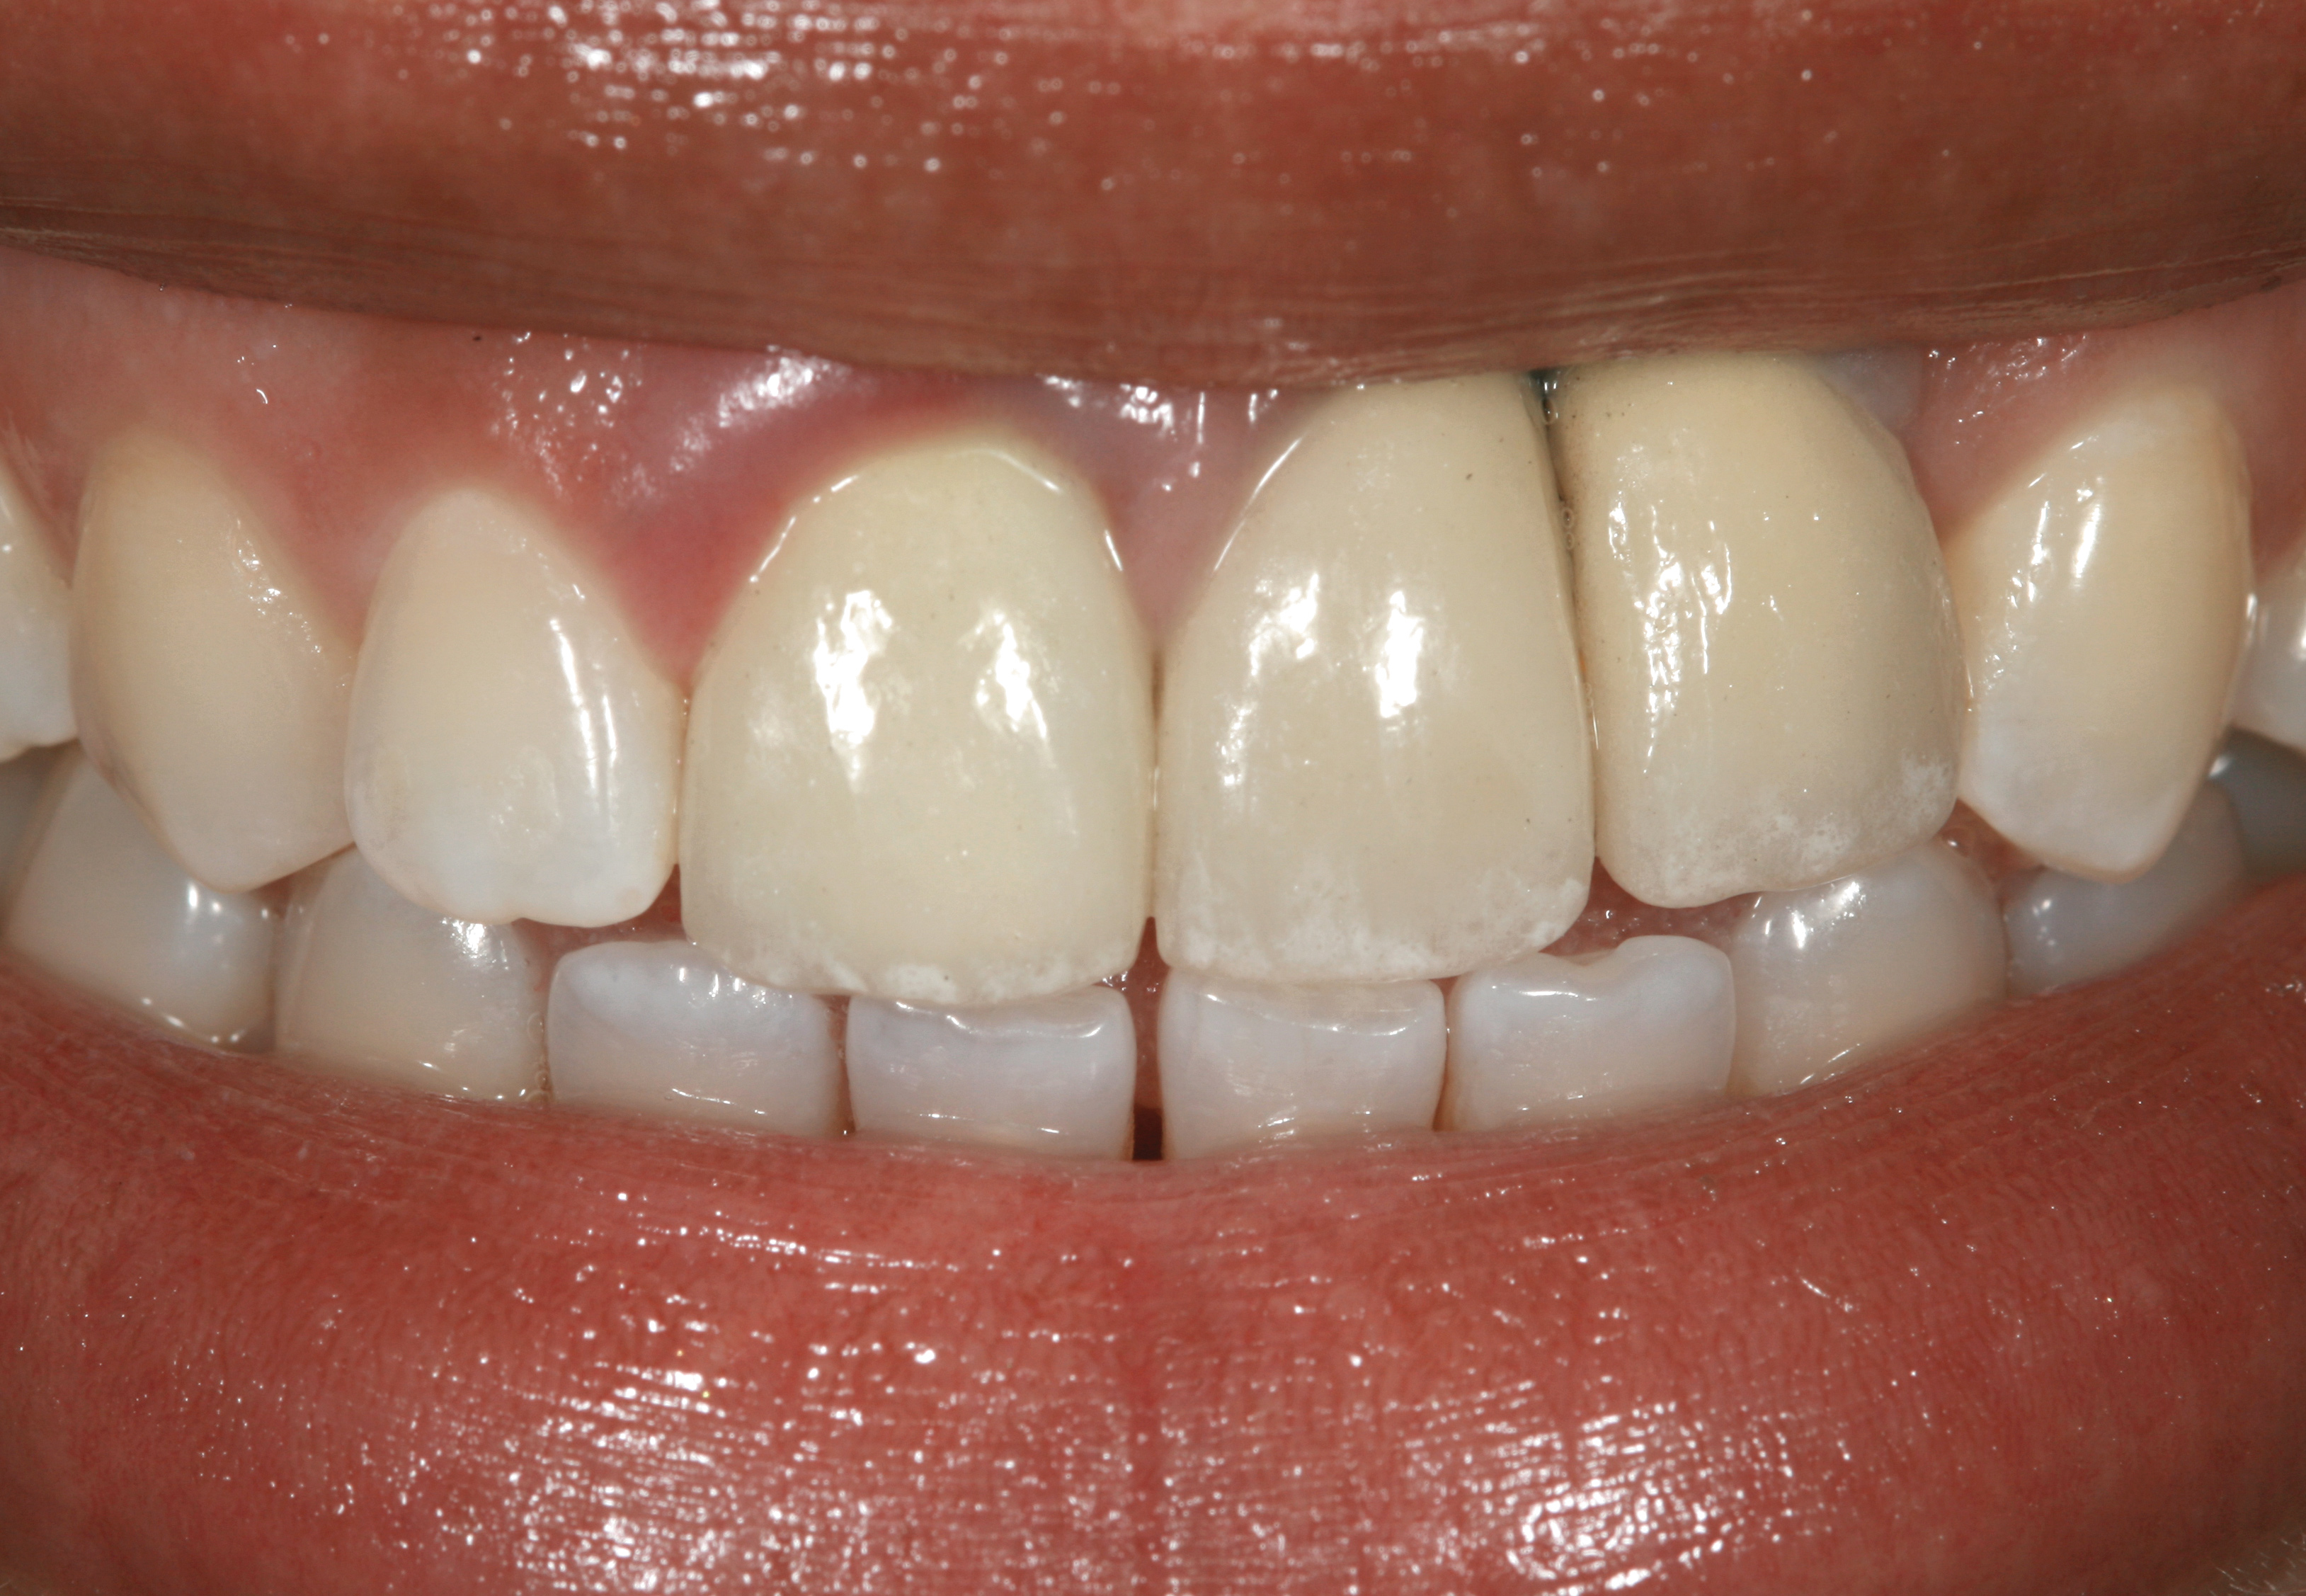

Fig 3. A patient presented with a high smile line and midfacial recession of the maxillary right lateral incisor as evidenced by the increased tooth length compared with the contralateral lateral incisor.

Figure 3

Fig 4. Intraoral view of tooth No. 7 with the gingival zenith more apical than the adjacent central incisor and canine tooth.

Figure 4